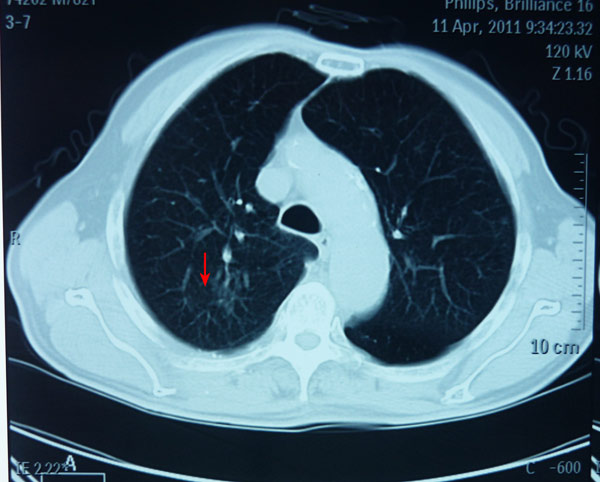

廖老右上肺癌治疗前

射波刀治疗后一年肿块消失